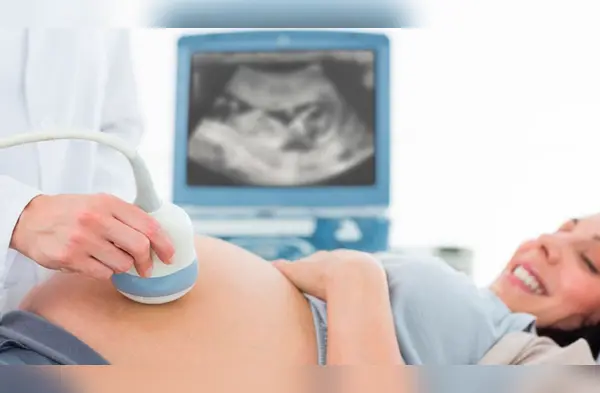

El embarazo es una de las etapas más importantes que vive una mujer, por lo que requiere de ciertos cuidados para beneficio de la salud del bebé como el de futura madre, por lo que se recomienda que se realicen una ecografía genética

La ecografía genética es el examen ecográfico más importante que se debe realizar toda gestante entre las 11 a 14 semanas de embarazo. Este examen se realiza con el objetivo de visualizar imágenes ecográficas anormales, los llamados “marcadores ecográficos para anomalías cromosómicas”, que se clasifican en: transluscencia nucal, hueso nasal, ductus venoso y regurgitación tricuspídea, los cuales pasan por un proceso de medición, permitiendo conocer el nivel de riesgo.